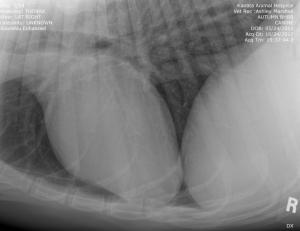

UPDATE: I know I have much to update in BHRR's Autumn's blog and before I go to bed in the wee hours; I shall update her blog plus add photos from her x-rays – taken of both legs, chest, back, legs, heart etc. on October 24th, 2012 and you can find them below! 🙂

YET, today is a very special day for her…..SPAY day! She is still thin, no doubt about that yet, we are in that catch twenty-two….due to the hormones, she continues to lactate and be in a state food going to produce milk instead of putting in weight. YET, being thin, makes it more risky to spay. 🙁 She needs to gain weight yet, cannot really well as she is in this false pregnany hormone out of balance state. So, we are about 10 or so more pounds that we were with her weight and the go ahead has been given to spay.

From there, we are putting our creative hats on as she will need two cruciate surgeries – $6,000-$7,000+ – and the specialist is still looking at those eyes and what is going to be best….